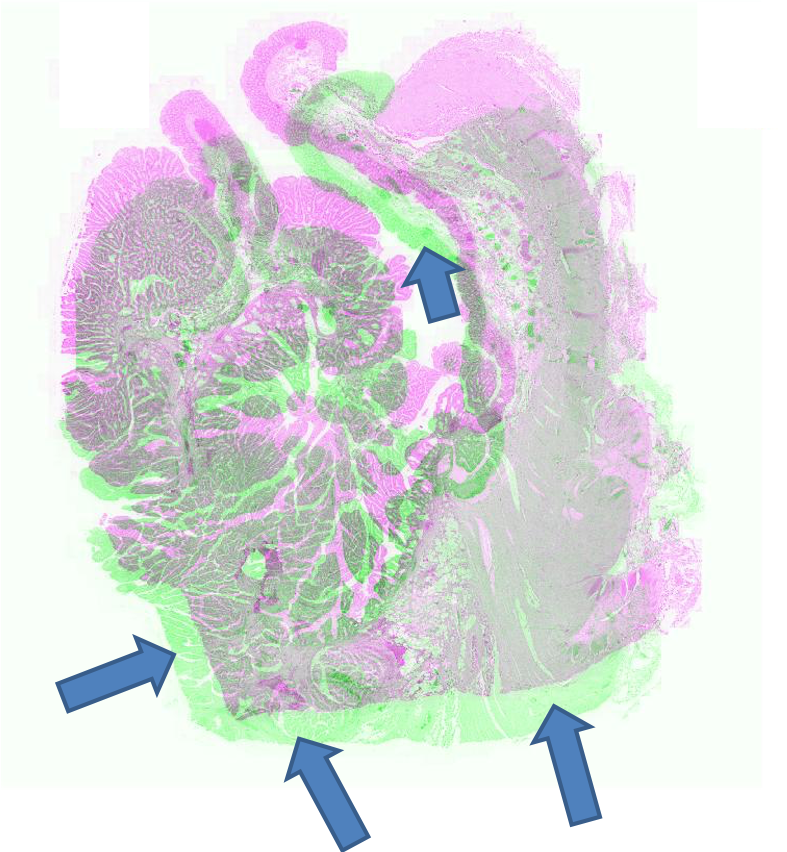

FigureΒ 2 shows the registration results for pathology images where we show the reference and floating images alongwith the misalignment images before registration and after registration using SR-Net and SR-Net. The misalignment is greatly reduced after registration using SR-Net while in the case of SR-Net there is still some resulting misalignment. This error can have significant consequences in the final diagnosis workflow. Hence the advantages of self-supervised segmentation maps are quite clear.

![]() |

| (a) | (b) | (c) | (d) | (e) |